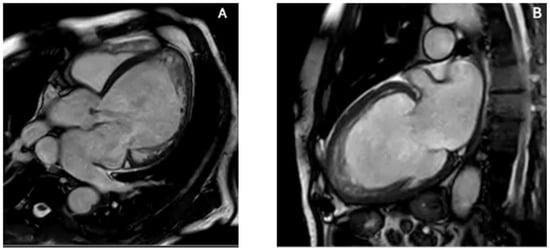

Cardiac amyloidosis (CA) results from myocardial deposition of misfolded fibrillary proteins demonstrating Congo Red affinity and yellow–green birefringence under polarized light [90,91]. Among the over 30 amyloidogenic proteins, immunoglobulin light chains (AL) and transthyretin (TTR)—either hereditary (vATTR) or wild-type (wtATTR)—represent the most frequent and significant for cardiac involvement [92]. Penetrance varies by TTR mutation, wtATTR predominantly affects the heart, and nearly 70% of AL patients develop cardiac disease [90]. Amyloid infiltration leads to progressive myocardial thickening, diastolic dysfunction, and heart failure, often mimicking hypertensive heart disease or hypertrophic cardiomyopathy in early stages [57], and is now explicitly recognized among key etiologies of HFpEF in contemporary heart failure guidelines [93]. Echocardiography is the first-line tool that raise suspicion of CA. It typically shows increased wall thickness, low-voltage ECG–echo mismatch, biatrial enlargement, valvular thickening, and elevated filling pressures [57,94]. GLS, assessed through speckle-tracking, demonstrates relative apical sparing (RELAPS), with less impaired apical strain compared with basal segments [95,96], likely related to differential amyloid deposition or remodeling gradients [97]. An apical-to-mid-basal LS ratio >1 provides high sensitivity (93%) and specificity (82%) for distinguishing CA from other LV hypertrophy etiologies [90]. Careful avoidance of apical foreshortening is essential, as this may falsely exaggerate apical strain [98]. ATTR is typically associated with concentric hypertrophy with RELAPS. On the other hand, atypical apical variants are increasingly recognized in AL amyloidosis. Cytotoxic light chains may promote microvascular dysfunction, necrosis, and replacement fibrosis, producing heterogeneous strain patterns—including true apical involvement and “reverse apical sparing” [90]. The appearance of atypical apical amyloid infiltration on contrast TTE and the corresponding strain abnormalities are illustrated in Figure 5. Apical thickening, fibrosis, and intracavitary thrombus formation may occur, contributing to low-flow states and embolic risk even in sinus rhythm [99]. These thrombi may be challenging to detect on standard TTE, necessitating Contrast TTE or CMR. Echocardiographic features suggestive of apical involvement include granular apical thickening, apparent apical pseudo-obliteration, loss of RELAPS, and difficulty in distinguishing thrombus from infiltrated myocardium [100]. CMR provides critical tissue characterization, and LGE, native T1 mapping, and extracellular volume quantification reveal amyloid deposition, fibrosis, and apical involvement [101]. The prognostic and diagnostic value of these mapping parameters has been confirmed in multicenter cohorts and meta-analyses [90,102]. CMR also differentiates true apical obliteration—typical of EMF—from pseudo-obliteration due to massive amyloid infiltration [102,103,104]. Feature-tracking CMR confirms longitudinal strain impairment with relative apical sparing, paralleling echocardiographic findings [105]. Integration of echocardiography, strain imaging, and CMR is crucial because of the aggressive course of AL amyloidosis and the increased risk of thrombotic and embolic complications.

Figure 5. Echocardiographic features of atypical apical involvement in cardiac amyloidosis. In cardiac amyloidosis, apical thickening may mimic ApHCM or focal fibrosis, but multimodality echocardiographic assessment—particularly contrast TTE combined with strain analysis—reveals characteristic patterns that help differentiate infiltrative disease from other apical pathologies. (A) Contrast-enhanced TTE (apical two-chamber view) demonstrates improved endocardial border delineation and increased biventricular wall thickness with a granular sparkling myocardial texture, supportive of atypical apical amyloid infiltration. (B) Speckle-tracking-derived bull’s-eye plot shows disproportionately reduced apical longitudinal strain (“reverse apical sparing”), a deformation pattern associated with apical AL amyloidosis and distinct from the classic RELAPS pattern of ATTR. The combination of granular apical texture, contrast-enhanced visualization, and apex-predominant strain reduction differentiates amyloidosis from ApHCM (where apical strain is typically preserved or only mildly reduced), ischemic scarring (territorial pattern), and LVNC (deep perfused recesses rather than homogeneous thickening). Original images from our institution (single patient).